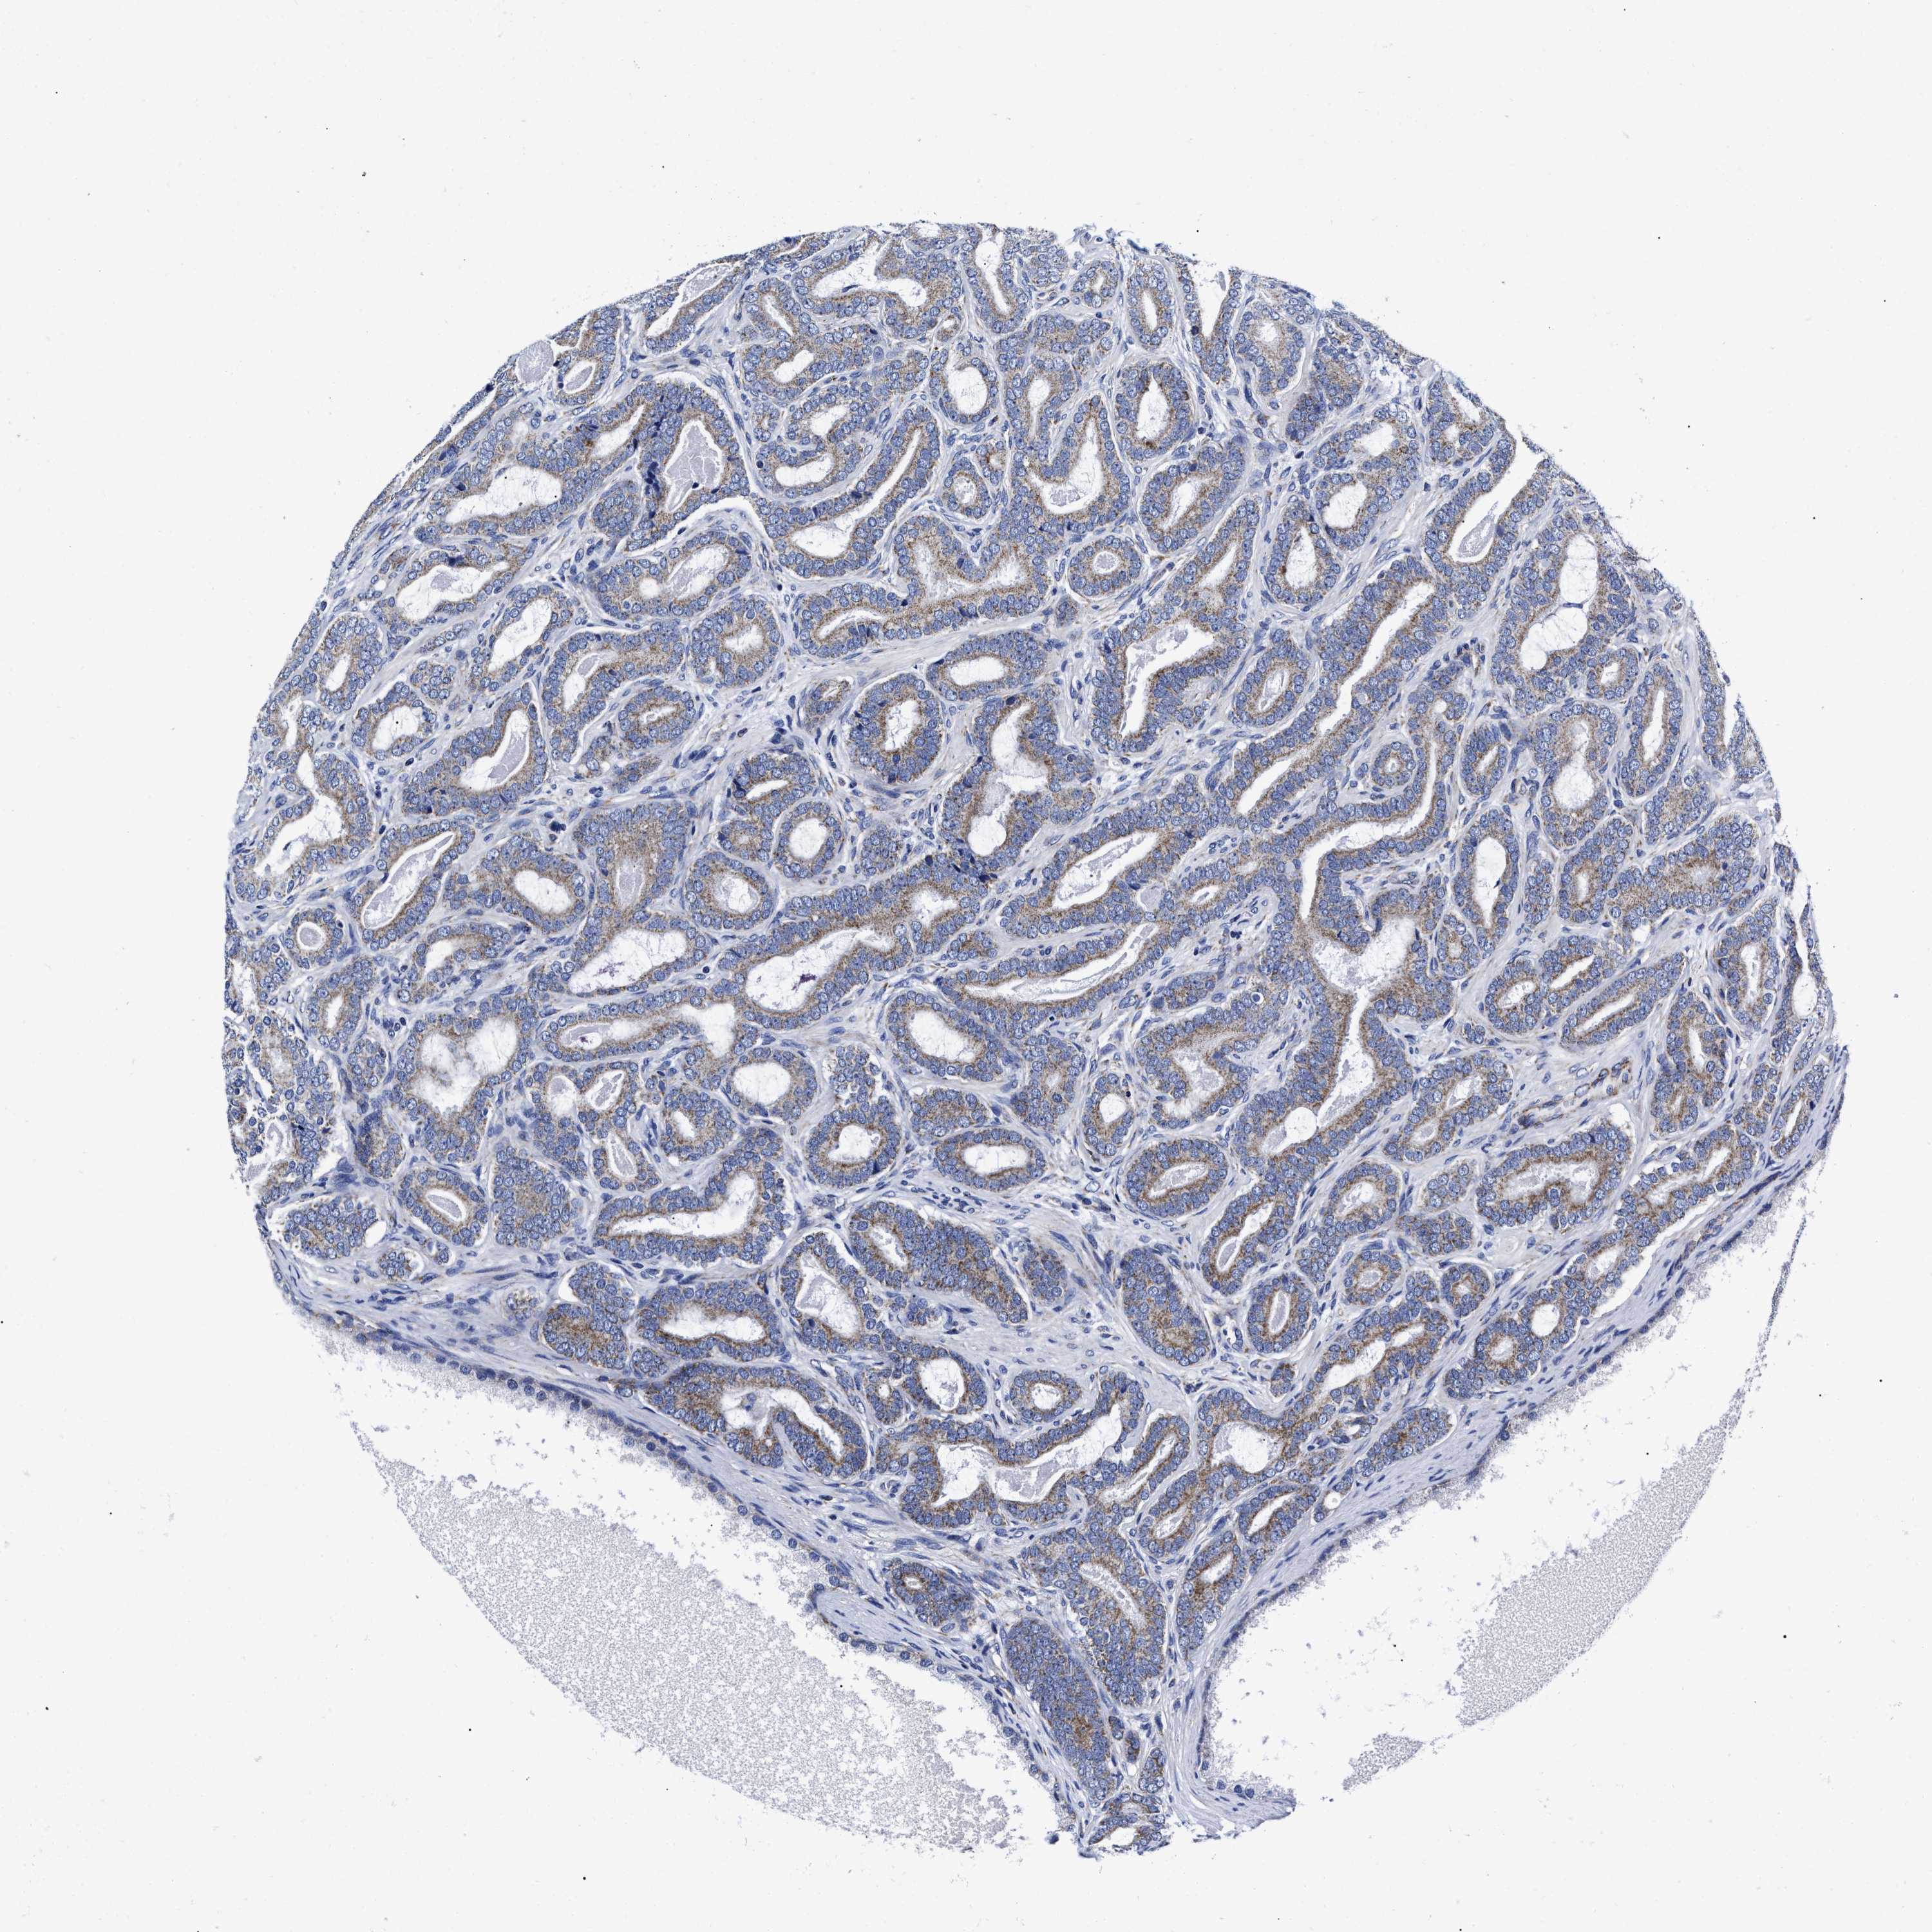

PROSTATE CANCER - Protein expressioni

A mouse-over function shows sample information and annotation data. Click on an image to view it in a full screen mode. Samples can be filtered based on level of antibody staining by selecting one or several of the following categories: high, medium, low and not detected. The assay and annotation is described here.

Note that samples used for immunohistochemistry by the Human Protein Atlas do not correspond to samples in the TCGA dataset.

Antibody stainingi

Antibody staining in the annotated cell types in the current human tissue is reported as not detected, low, medium, or high, based on conventional immunohistochemistry profiling in selected tissues. This score is based on the combination of the staining intensity and fraction of stained cells.

Each image is clickable and will lead to virtual microscopy that enables deeper exploration of all samples and also displays staining intensity scores, fraction scores and subcellular localization as well as patient and tissue information for each sample.

Antibody HPA020961

Antibody HPA059109

Staining

High

Medium

Low

Not detected

Intensity

Strong

Moderate

Weak

Negative

Quantity

>75%

75%-25%

<25%

None

Location

Nuclear

Cytoplasmic/membranous

Cytoplasmic/membranous,nuclear

Adenocarcinoma, High grade

Adenocarcinoma, Low grade